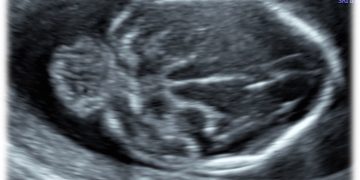

Casi del Mese di Marzo 2023

Cari soci, finalmente online le soluzioni dei casi per il mese di Marzo!!! Grazie a Ilaria Fantasia e Gabriele Saccone!! Caso 1 [pdf-embedder url="https://www.sieog.it/wp-content/uploads/2023/03/caso-clinico-Fantasia-risposta-marzo-2023.pdf" title="caso...